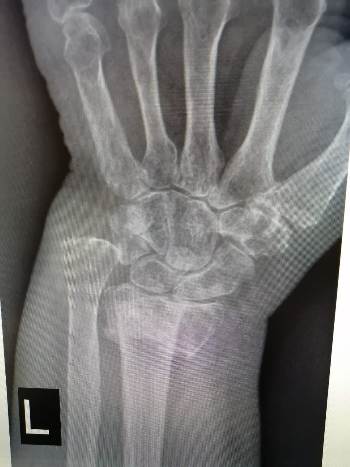

Пациентка Шурубекова В., 1965 г.р., обратилась в клинику ВиТерра к врачу травматологу-ортопеду с жалобами на боли, деформацию, отёк, ограничения движений в левом лучезапястном и правом голеностопном суставах.

Со слов пациентки, 3 недели назад она упала на улице со ступеньки. Обращалась к костоправу, затем в поликлинику по месту жительства, ожидаемого эффекта не было.